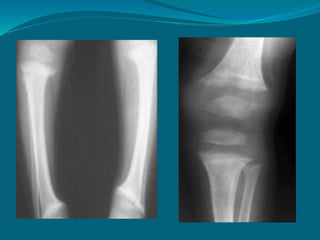

RADIOGRAPHIC FINDINGS

X-RAY – LOOSER ZONE